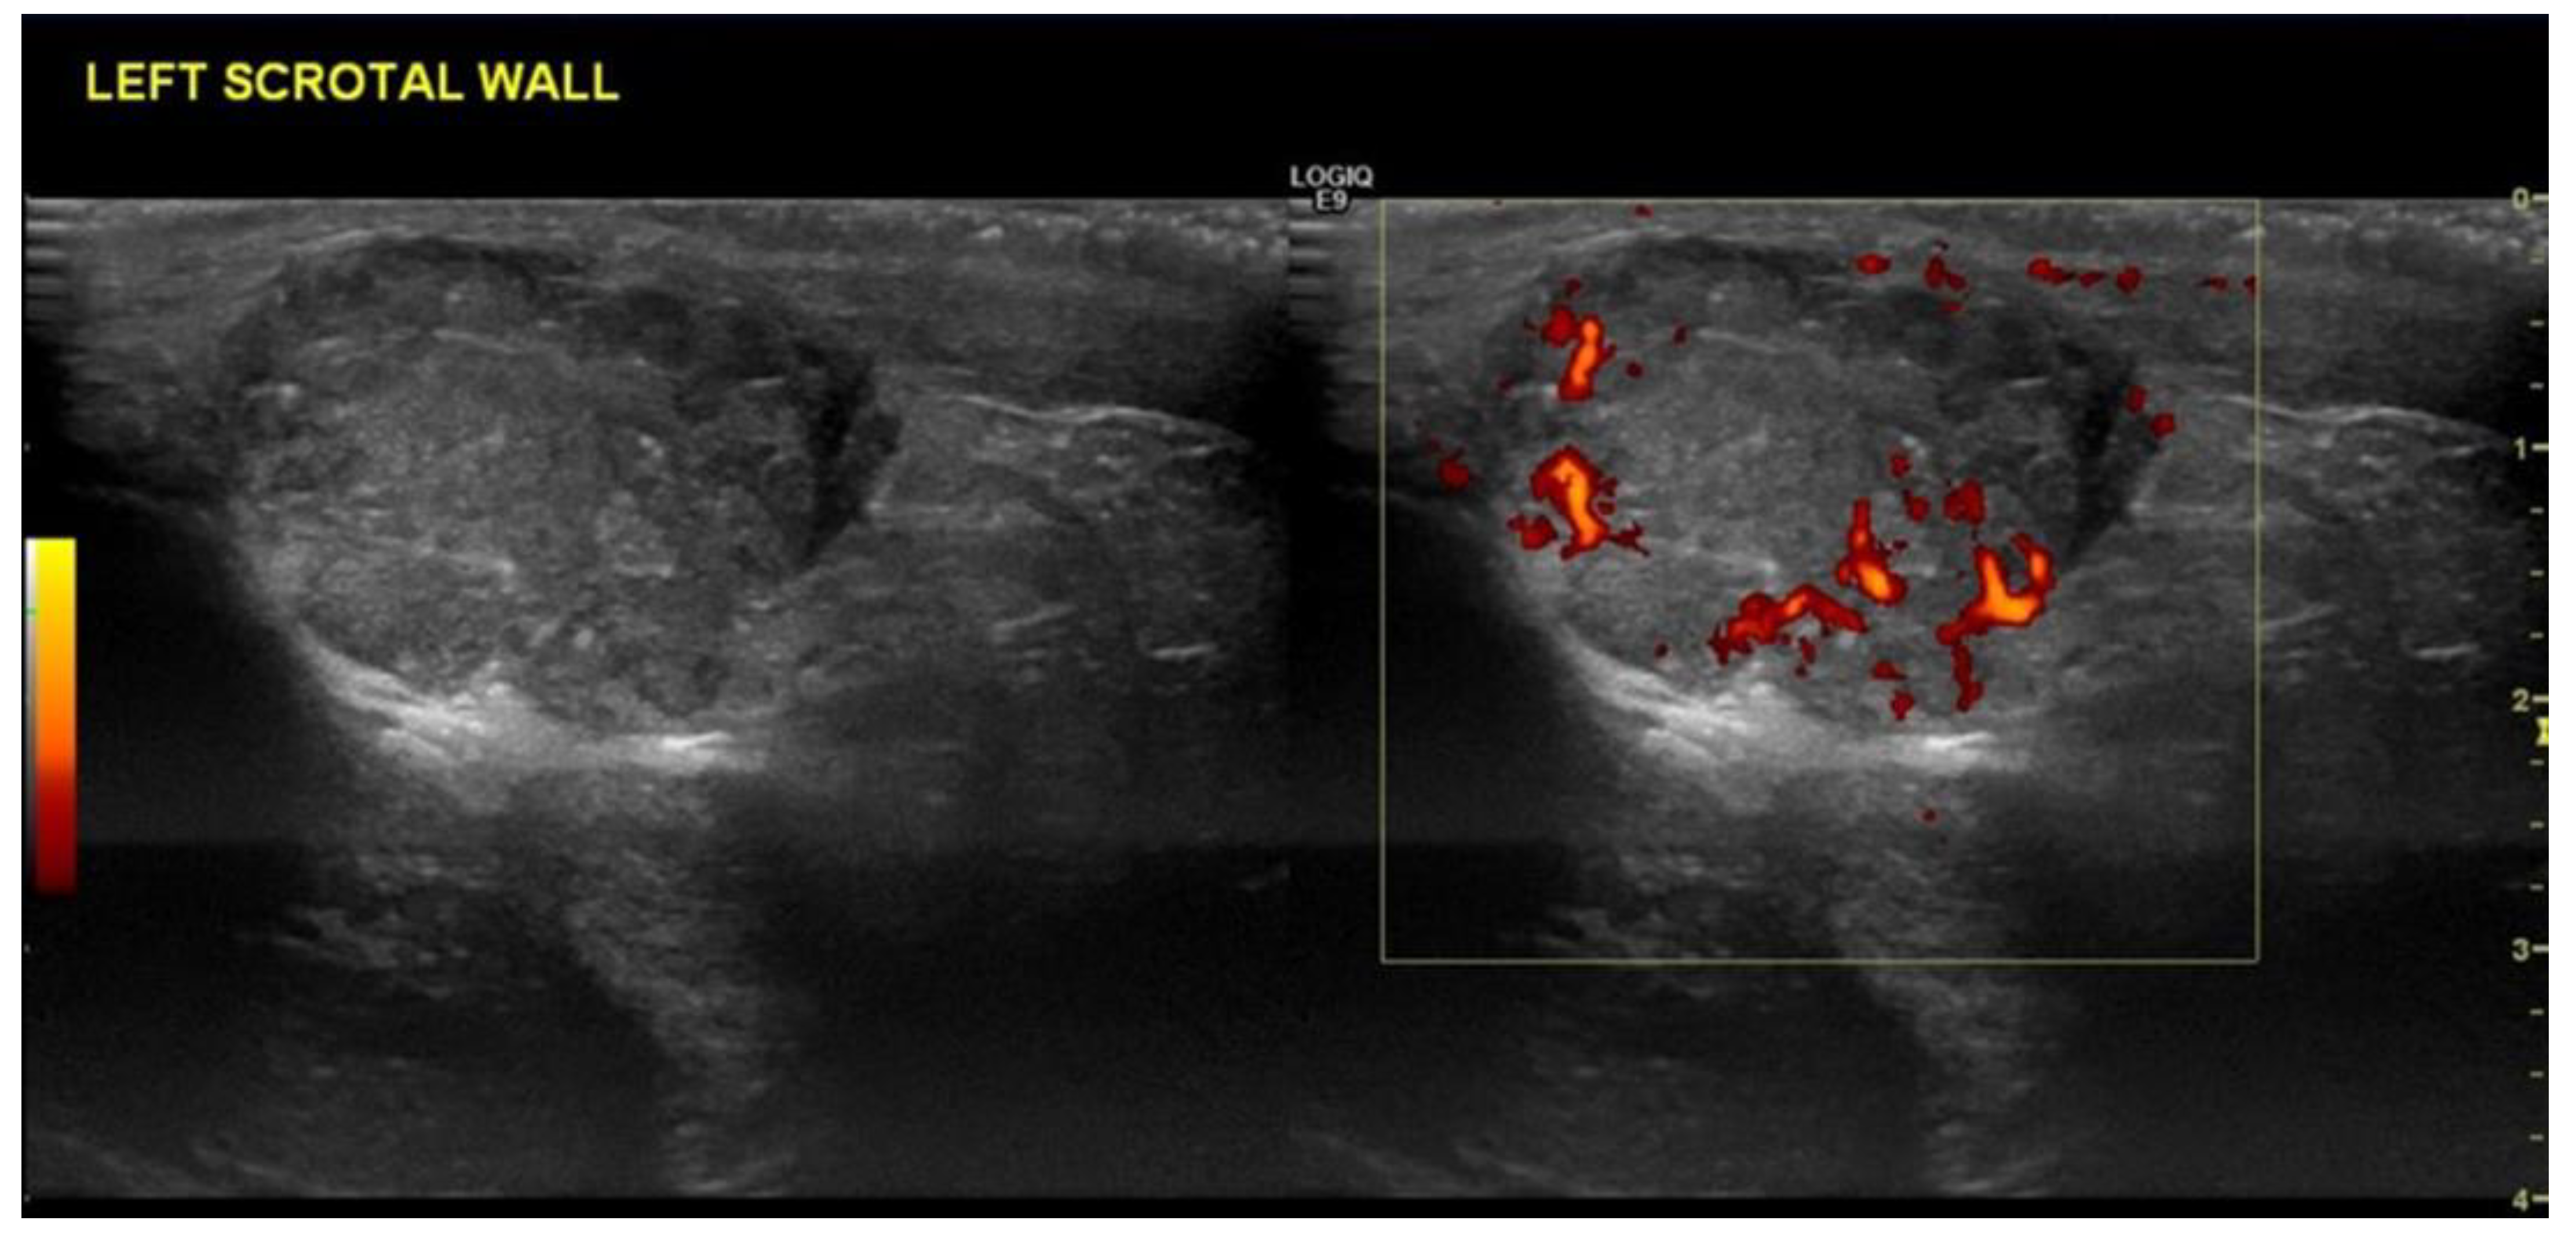

4.2. Non-Seminomatous Germ Cell Tumour (NSGCTs)

| Non-seminomas | Heterogenous Irregular margins Cystic and calcification components seen commonly |